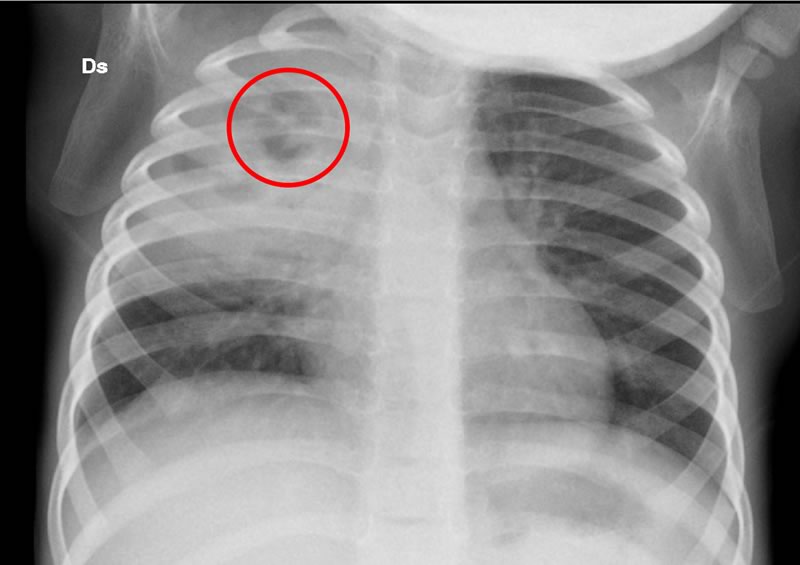

Ripete la Radiografia del torace che evidenzia in sede centrale al focolaio un'area di pneumatizzazione (Figura 3).

Opacità al campo superiore medio di dx con area di relativa radiotrasparenza nei settori più craniali, da possibile iniziale cavitazione. Figura 4